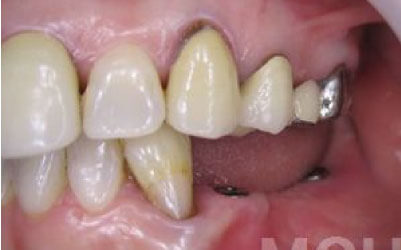

前歯はもともと骨が薄く、歯が抜けると時間の経過とともにさらに骨が痩せてきてしまうので、インプラント治療の難易度が高い場所です。

ただ結論からお話すると、インプラント治療は可能です。

なぜなら、もし仮に骨が薄くても、骨の治療によって厚みが増せば、安全にインプラント治療が行えるからです。

なお、前歯のインプラント治療をご希望の方には、注意していただきたい点が4つほどあります。

1)インプラント治療を行う前に、骨の治療が必要かもしれません。

2)骨の治療から始めると、その分、治療期間が長くなります。

3)骨の治療は、通常のインプラント治療よりも難易度が高いため、経験の豊富な先生やインプラント認定医のいる歯科医院で治療を受けることをお勧めします。

4)骨の状況をしっかり把握するためにも、CT撮影が必須となります。